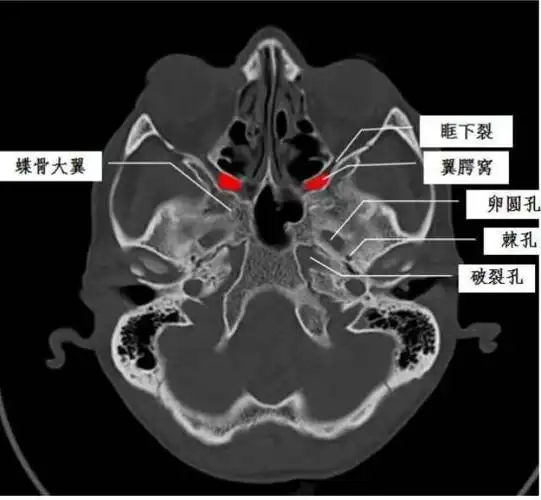

翼腭窝的ct影像解剖